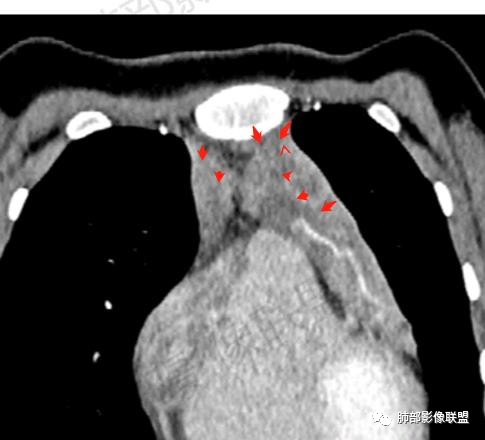

飞鹰行动:

青年女性,贫血病史,前纵隔占位,增强病灶中度强化,可见血管包埋,考虑恶性病变,淋巴瘤,生殖类肿瘤待排除。

青年女性,前纵隔不规则软组织肿块,呈结节样融合,密度不均匀,见多发坏死,肿块包绕肺动脉主干,呈不均匀强化,多发低密度坏死无强化,内可见血管穿行,伴腋窝淋巴结肿大,考虑淋巴瘤可能大

年轻女性,乏力贫血,前中纵隔肿块,有多结节融合趋势,中度强化,坏死区边界清楚,左内乳淋巴结及双腋窝淋巴结肿大,考虑淋巴瘤。

年轻女性 前中纵隔多发肿块,质软,相互融合,向下侵及心包。增强不均匀强化,内见血管影。双侧腋下多组淋巴结肿大。考虑恶性,淋巴瘤,胸腺瘤。

前纵隔占位,多结节融合,内见坏死,坏死边缘清晰,内乳淋巴结及腋窝淋巴结肿大,包绕血管,贫血,年轻女性,考虑淋巴瘤,鉴别生殖细胞瘤,肉瘤

青年女性,前纵隔肿块,呈多结节融合状,内多发囊变坏死区,血管包埋,双侧腋窝淋巴结肿大,考虑胸腺淋巴瘤可能性大

前纵隔软组织肿块,融合,见多发坏死,强化不均,包绕血管,腋窝淋巴结肿大,考虑淋巴瘤

女,27岁,贫血,前纵隔不规则形软组织密度肿块影,边界欠清晰,其内密度不均匀,部分血管包埋,双侧腋窝见肿大淋巴结,考虑淋巴瘤可能。

前纵隔胸腺结节及肿块,融合,包绕大血管,不均匀强化,多发坏死,边界清,血管包埋,双侧腋窝肿大淋巴结,考虑淋巴瘤

前纵隔不规则肿块,似多结节融合,包绕血管,不规则强化,考虑淋巴瘤

年轻女性,前纵隔多发淋巴结肿大融合,包绕心脏大血管,血管穿行。伴中纵隔、双侧腋窝淋巴结增大,考虑恶性,淋巴瘤可能大。

前纵隔占位,多结节融合,血管穿行,侵犯心包,考虑淋巴瘤

晨读前纵隔多发结节融合成团,包绕大血管,增强内有血管穿行,考虑淋巴瘤,鉴别胸腺肿瘤。

前上纵隔不规则肿块,多结节融合,边界欠清,多发坏死,腋窝多发大小不等淋巴结肿大,年轻女性,考虑恶性,淋巴瘤首先考虑,胸腺肿瘤不除外

前纵隔占位,多结节融合,多发坏死,边界欠清,血管包埋其中,不均匀强化腋窝见增大淋巴结影,首先考虑淋巴瘤,生殖类肿瘤待排!

前纵隔不规则肿块,结节融合,边界不清,平扫密度欠均匀,增强多发低密度坏死,血管穿行,腋窝多发大小不等淋巴结肿大,年轻女性,贫血,发热。考虑恶性:胸腺癌。其次淋巴瘤

纵隔肿块,密度不均,边界模糊,侵及心包。增强不均匀强化,内见血管影。双侧腋下多组淋巴结肿大。考虑淋巴瘤,胸腺瘤,鉴别结核。

纵隔多发结节堆积 塑型生长  质软 边界不清 强化不均  双侧腋窝淋巴结肿大

年轻女性,贫血伴乏力,前纵隔占位,多发结节融合成块,爬孵感,边界模糊,不均匀强化,中心坏死,内可见血管造影,部分侵犯心包,双侧腋窝多发肿大淋巴结,首先考虑淋巴瘤

年轻女性,贫血,CT示前纵隔团片状软组织占位,多结节堆积感,塑形生长,边界欠清,包绕大血管及心包,增强明显不均匀强化,内见血管漂浮。纵隔4R,5,7区及双侧腋窝多发肿大淋巴结,综合考虑为淋巴瘤可能

前纵隔不规则肿块,多结节融合,边界欠清,延周围脂肪间隙生长,包绕主动脉及肺动脉血管,平扫密度欠均匀,增强扫描可见多发低密度坏死,并可见一条血管穿行,腋窝多发大小不等淋巴结肿大,年轻女性,考虑恶性:淋巴瘤,胸腺癌,肉瘤,浆细胞瘤

前纵隔占位,血管包埋,轻中度强化,考虑淋巴瘤。

年轻,前纵隔多结节融合样大肿块,包绕心脏大血管,伴中纵隔、双侧腋窝淋巴结增大,考虑淋巴瘤

女,27,间断头晕、乏力3年,左眼视物模糊2月。贫血。胸部CT:前纵隔不规则肿块,多结节融合,边界不清,沿主动脉及肺动脉间隙生长,平扫密度欠均匀,增强扫描可见多发低密度坏死,纵隔血管供血穿行,腋窝多发大小不等淋巴结肿大。考虑恶性病变,胸腺癌?肉瘤?淋巴瘤?鉴别胸腺瘤、结节病等。

前纵隔和双侧腋窝多发的淋巴结肿大,前纵隔为甚,融合呈中等强化,部分坏死呈低密度,包埋肺动脉主干和左心缘,融合斑块状,内见血管飘浮特点,前纵隔脂肪间隙混浊,首选淋巴瘤!

临床:年轻女性,慢性病程,多系统病变,头晕,贫血,视物模糊。

CT:定位纵膈病变,前中纵隔多发肿块,质软,塑形,密度不均匀,边界清楚。增强不均匀强化,坏死边界清楚,血管漂浮征。双侧腋下多组淋巴结肿大,明显异常强化。

2.影像显示前纵隔不规则块状影,依势贴附心脏大血管旁,密度不均,边界不甚清楚,有结节融合感。

3.病灶轻度不均匀强化,可见血管穿行,散在液性低密度区。

双肺门未见肿大淋巴结。

4.双侧腋窝区见增大淋巴结,边界清楚。

1.年轻女性,前纵隔不规则块状影,密度不均,边界不甚清楚,有结节融合感,轻度不均匀强化,可见血管穿行,最常见最符合的无疑是淋巴瘤!